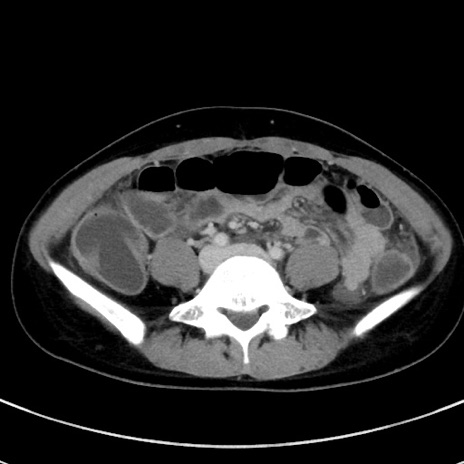

症例17(横断像)

【症例】20歳代女性

【主訴】嘔吐、下腹部痛

【現病歴】昨日夕食後に嘔吐し下腹部痛が出現。本日になっても嘔吐持続し改善しないため来院。

【身体所見】意識清明、BT 37.2℃、BP 108/67mmHg、腹部:平坦、やや硬、下腹部正中から右にかけて圧痛あり、反跳痛軽度あり、tapping pain(+)。

【データ】WBC 13600、CRP 14.94